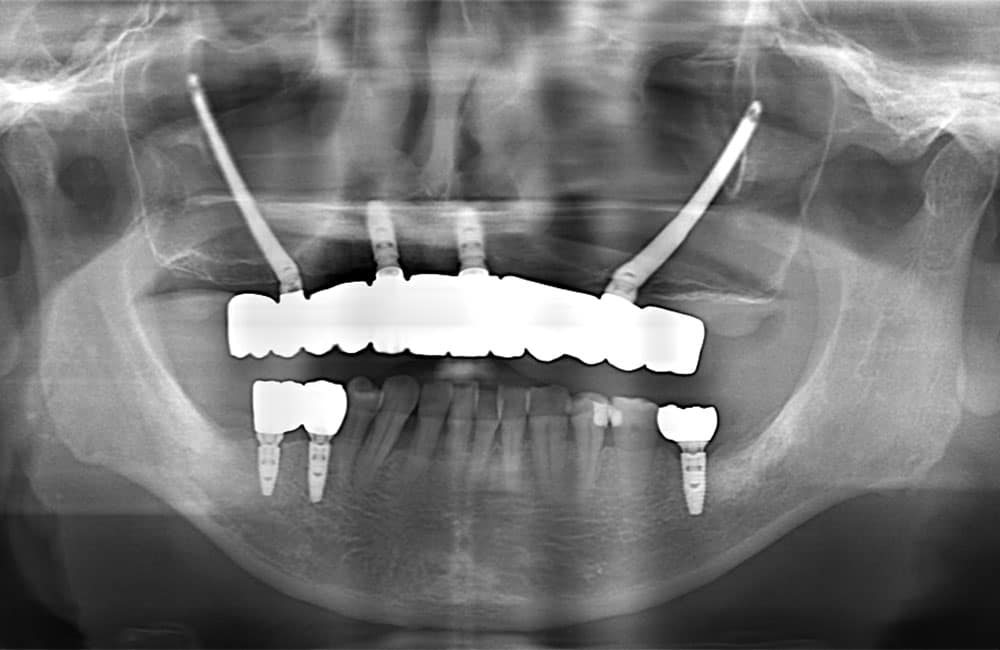

他院でザイゴマインプラント治療を受けた後、仮歯の噛み合わせが悪いため噛みづらく顔貌も変わってしまった。また頬に違和感を感じたため当院を受診。

術前のパノラマX線画像

術前のCT画像

左右のザイゴマインプラントが頬骨から大きく飛び出し頬を触ると違和感がある -

術後のパノラマX線画像

術後のCT画像

前方のインプラントは残し、他院埋入のザイゴマインプラントを除去し、同時に新しいザイゴマインプラントを適切な位置に再埋入を行っております。治療後数年経過しておりますが良好な状態を保っております。

| 治療期間 | 6ヶ月〜1年 |

| 治療方法 | 左右ザイゴマインプラント除去及び再埋入・上下仮歯(2回)及びフルジルコニア最終補綴物 |

| 治療費用 |

7,040,000円(税込) ※再手術費用・上下仮歯2回(1,540,000円)、及びフルジルコニア最終補綴物(5,500,000円) |

| リスク・副作用 | ザイゴマインプラント治療により、急性細菌性副鼻腔炎を起こす可能性があります。ザイゴマインプラントも通常のインプラント同様、メンテナンスを怠るとインプラント周囲炎を招く恐れがあります。 |